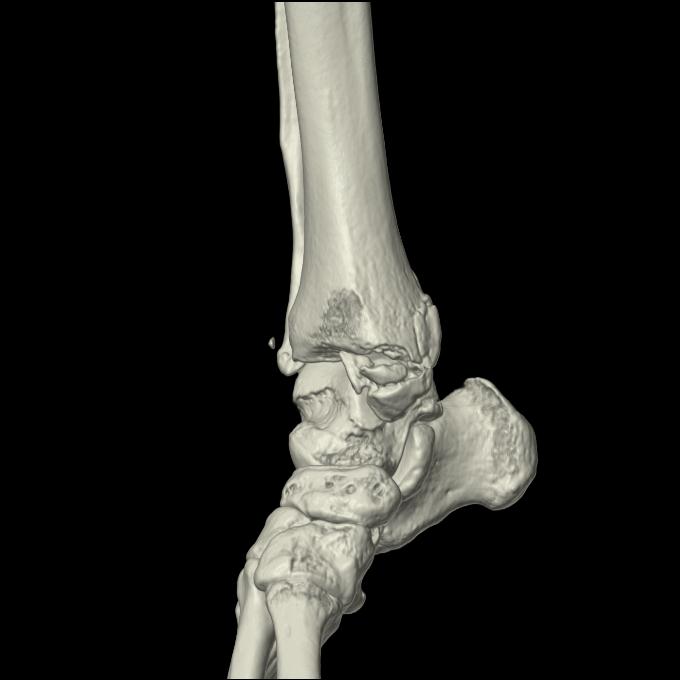

102755 1/4 2R 1/15 2R 右足関節 68歳女性 右三果脱臼骨折